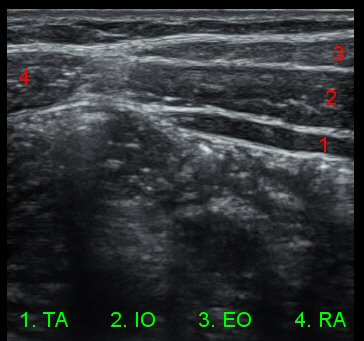

. ÃÖ±Ù ÃÊÀ½ÆÄ±â±â¸¦ ÀÌ¿ëÇÏ¿© ½Ç½Ã°£ÀûÀ¸·Î

ÄÚ¾î ±ÙÀ°À» °üÂûÇϸ鼭 ÄÚ¾î ±ÙÀ°À» ¿îµ¿½ÃŰ´Â ¹æ¹ýÀÌ ´ëµÎµÇ¾î ¿Ü±¹¿¡¼­ À̹Ì

³Î¸® ½ÃÇàµÇ°í ÀÖ½À´Ï´Ù

5)  ÄھƱÙÀ°À̶õ?